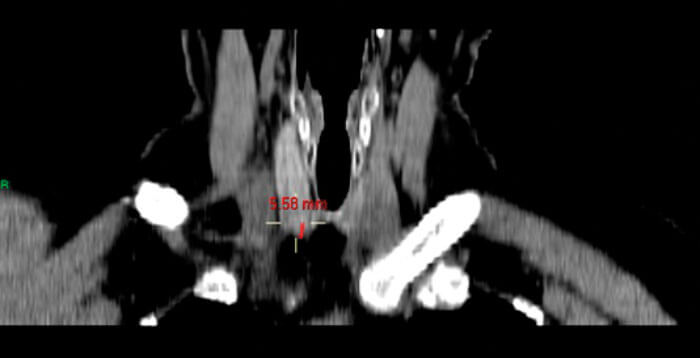

Using the PACS software, the corresponding CT images are viewed using multiplanar reconstruction (MPR). The PACS ruler is used to measure the following (see Figures 2-5).

- Size of the parathyroid gland in three dimensions.

- Distance from the cricoid to the parathyroid gland.

- Distance from posterior edge of thyroid to the parathyroid gland.

- Distance from the skin to the parathyroid gland.

Figure 3. Coronal CT image on MPR setting showing distance of PT gland from cricoid (26.37mm).